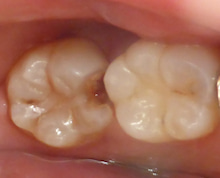

全部 虫歯をとりました。

こんなに 大きな穴が開いてしまいました。